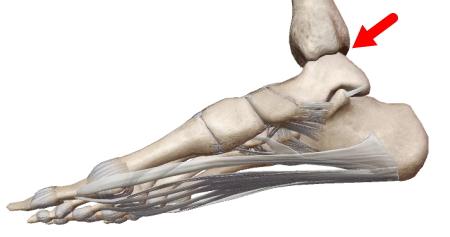

蝶番関節

| ドアの蝶板(丁番)に似た構造。溝状の凹面を持つ関節窩と円柱状の関節頭からなる1軸の関節。 膝関節、肘関節(椀尺関節)、距腿関節、指節間関節。 *膝関節は屈曲時に回旋できるので顆状関節(浅い球関節)の一面もあります。 |